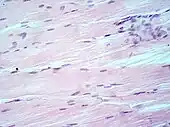

Main types of staining seen on H&E stain.

H&E is the combination of two histological stains: hematoxylin and eosin. The hematoxylin stains cell nuclei a purplish blue, and eosin stains the extracellular matrix and cytoplasm pink, with other structures taking on different shades, hues, and combinations of these colors.[5][6] Hence a pathologist can easily differentiate between the nuclear and cytoplasmic parts of a cell, and additionally, the overall patterns of coloration from the stain show the general layout and distribution of cells and provides a general overview of a tissue sample's structure.[7] Thus, pattern recognition, both by expert humans themselves and by software that aids those experts (in digital pathology), provides histologic information.

Hematoxylin principally colors the nuclei of cells blue or dark-purple,[6][15][14] along with a few other tissues, such as keratohyalin granules and calcified material. Eosin stains the cytoplasm and some other structures including extracellular matrix such as collagen[5][7][14] in up to five shades of pink.[8] The eosinophilic (substances that are stained by eosin)[5] structures are generally composed of intracellular or extracellular proteins. The Lewy bodies and Mallory bodies are examples of eosinophilic structures. Most of the cytoplasm is eosinophilic and is rendered pink.[10][15] Red blood cells are stained intensely red.